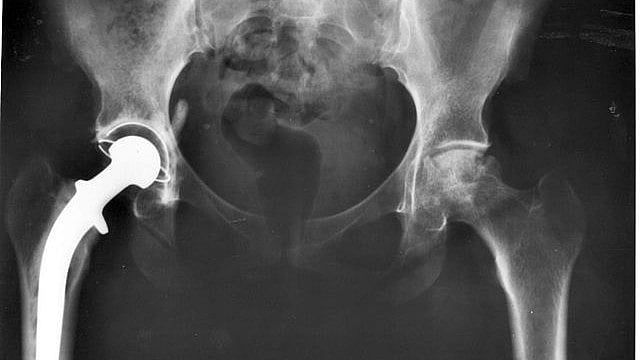

Hydrogel Injections Treat AntibioticResistant Infections After Hip After Knee Replacement Antibiotics You may need an antibiotic. If the antibiotic is inadvertently not administered, it may be given up to 2 hours after the procedure. Patients should not be exposed to the adverse effects of antibiotics when there is no evidence that such prophylaxis is of any benefit. Antibiotics before and after surgery. The most important known measures to lower the risk. After Knee Replacement Antibiotics.